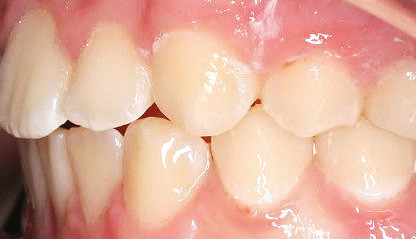

Klinisches Fallbeispiel 2 (Abb. 2a–y)

Distalbiss und tiefer Biss bei einem zwölfjährigen Mädchen. Die Behandlung erfolgte mit Invisalign und Precision Wings. Insgesamt waren zwei Schienensätze notwendig. Die Gesamtbehandlung dauerte 18 Monate.Bei der Planung des ClinCheck wurde der tiefe Biss vorwiegend über eine Intrusion der Unterkieferfront behoben, um die Lachlinie der Patientin nicht negativ zu beeinflussen. Die Oberkieferfront wurde nur retrudiert, jedoch vertikal nicht intrudiert. Während der Phase des Mandibular Advancement wurde die Wirkung der Precision Wings durch den Einsatz von Klasse II-Gummizügen unterstützt. Schlussendlich wurde auch der hängenden Okklusionsebene durch eine einseitige Intrusion der Molaren im ersten Quadranten Rechnung getragen.